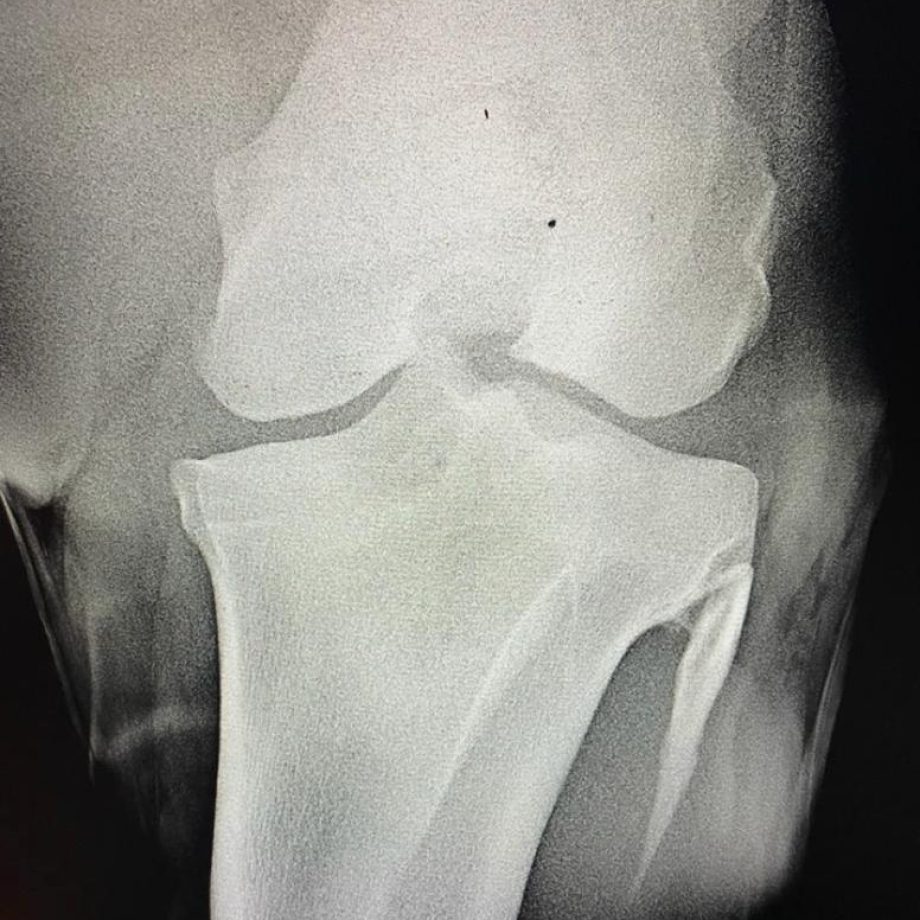

L’esame radiografico, che è quello più comune, è utile per verificare la presenza di difetti non visibili ad occhio nudo e, normalmente, interessa i piedi e gli arti del cavallo con un numero molto variabile di radiografie eseguite in accordo con l’acquirente sulla base di un preventivo costi da sostenere da parte di quest’ultimo.

Nella valutazione delle anomalie riscontrabili nelle lastre è essenziale tenere in considerazione l’età del cavallo e la sua destinazione d’uso.

Ad esempio, nei cavalli è comune riscontrare la presenza di frammenti osteocartilaginei (cosiddetti chip articolari verosimilmente legati a osteocondrosi).

A pari visita clinica la presenza di osteocondrosi in un soggetto giovane può avere sull’acquisto un impatto diverso rispetto a un cavallo in età più avanzata.

Simile discorso si può fare nella valutazione di una lastra al piede di un cavallo con alterazioni radiografiche dell’osso navicolare (frequente punto di confronto-discussione) in un cavallo giovane di 5-6 anni piuttosto che in un soggetto adulto di 13-14 anni.

A livello radiografico i difetti, le alterazioni della norma e le varianti anatomiche riscontrabili possono essere molti e diversi, ma non necessariamente patologici, sintomatici al momento della visita o considerabili sempre fattori di rischio per l’acquisto.